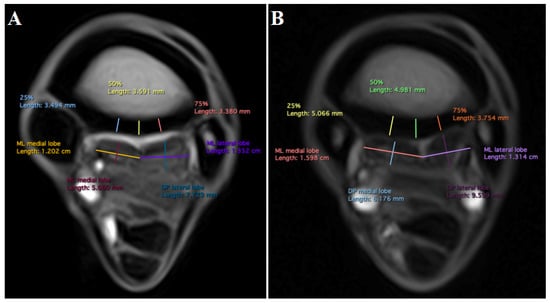

| SL ML Width—DP Depth | |||||||

|---|---|---|---|---|---|---|---|

| Level | ML Width | DP Depth | MD [mm] | p Value | 95% CI [mm] | ||

| Mean [mm] | SD [mm] | Mean [mm] | SD [mm] | ||||

| 3 cm distal to CMCJ | |||||||

| SL medial lobe | 14.3 | 1.8 | 7.2 | 1.3 | 7.1 | <0.01 * | 6.5, 7.7 |

| SL lateral lobe | 13.0 | 1.0 | 9.2 | 1.4 | 3.8 | <0.01 * | 3.44, 4.2 |

| 5 cm distal to CMCJ | |||||||

| SL medial lobe | NNDD b | ||||||

| SL lateral lobe | 11.6 | 1.3 | 8.0 | 1.0 | 3.6 | <0.01 * | 3.0, 4.1 |

| SL medial lobe—lateral lobe | |||||||

| level | medial lobe | lateral lobe | MD [mm] | p-value | 95% CI [mm] | ||

| ML | 14.3 | 1.8 | 13.0 | 1.0 | 1.3 | <0.01 * | 0.7, 2.0 |

| DP | 7.2 | 1.3 | 9.2 | 1.4 | −2.0 | <0.01 * | −2.5, −1.4 |

| ML | 12.3 | 1.5 | 11.6 | 1.3 | 0.7 | 0.7 | −0.1, 1 |

| DP | NNDD d | ||||||